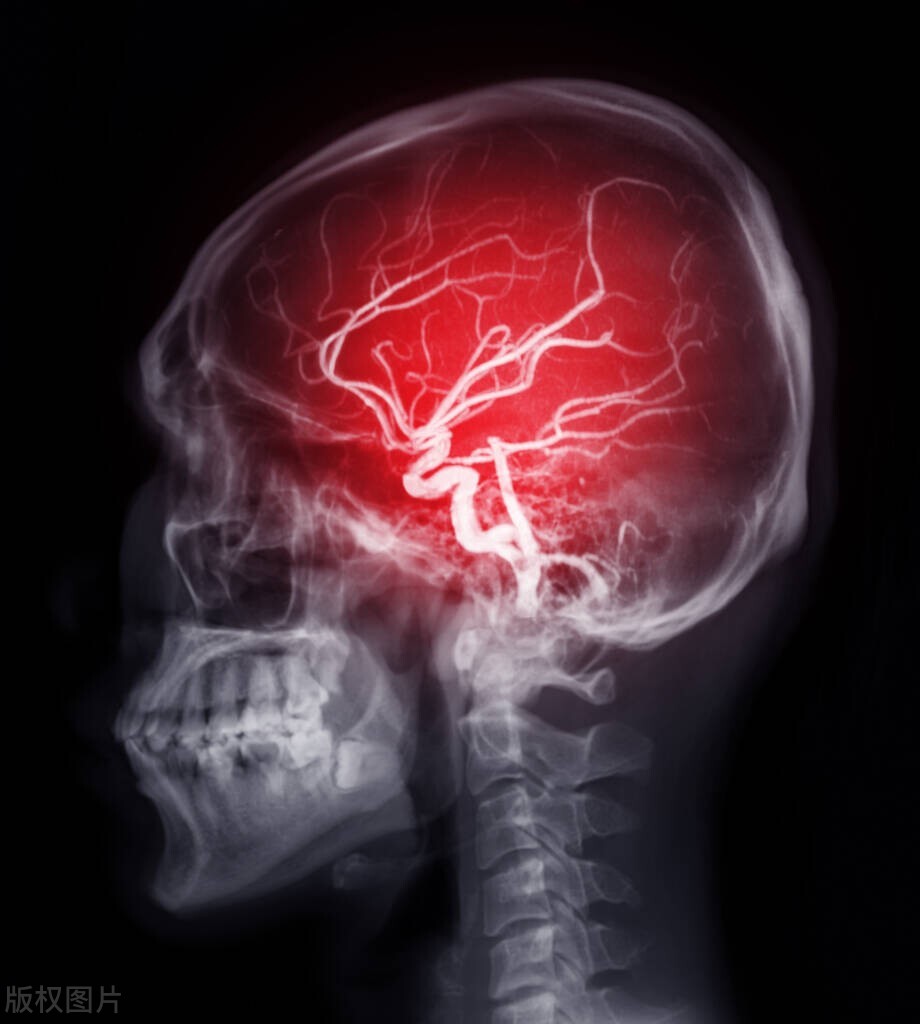

观察了半小时后好在没有更为糟糕的问题出现,血压也降到了185/97头痛的症状改善。继续给她进行治疗,经过这次她似乎有点重视血压问题了,不过在一旁的儿子似乎依旧不是那么在意。我开始跟她说高血压要规范治疗,一般需要长期服用降压药,虽然每天都要吃但其实也不会花费太多钱,特别是相对于对此不管不顾可能导致的脑卒中,血压太高了就像水管里的水压大水管会爆掉一样,高血压也会有可能把血管压爆,特别是我们大脑里的血管相对比较脆弱,最容易出意外,而且也非常危险。就像刚才你头痛就有可能是血压太高大脑血管有些承受不住了。

如果大脑的血管爆了严重可能直接就结束了生命,幸运一些的送往医院及时也还有机会,但是很多人因此会留下偏瘫、不会说话等严重的后遗症。这有多麻烦你可能想象不到,吃、喝拉、撒都离不开人照顾,更别提去干活帮衬家里了,说得直白点还可能会拖累家里人。我也不知道是因为担心母亲还是害怕母亲拖累自己,这个男人似乎开始重视这个问题,接二连三的问了一些关于高血压治疗的问题,言语间似乎是愿意认真对待高血压这个问题了。

虽然前面已经通俗易懂的说过了,这里在简单总结一下,会出现一过性脑血管痉挛,可致暂时性失语、失明、肢体运动障碍,甚至偏瘫。若是急性脑血管痉挛可使得其通透性增加而致脑水肿、颅内血压增高,脑小动脉硬化可形成小动脉瘤,还会导致脑血栓或脑出血,出现头晕、失语、肢体麻木、发生偏瘫。